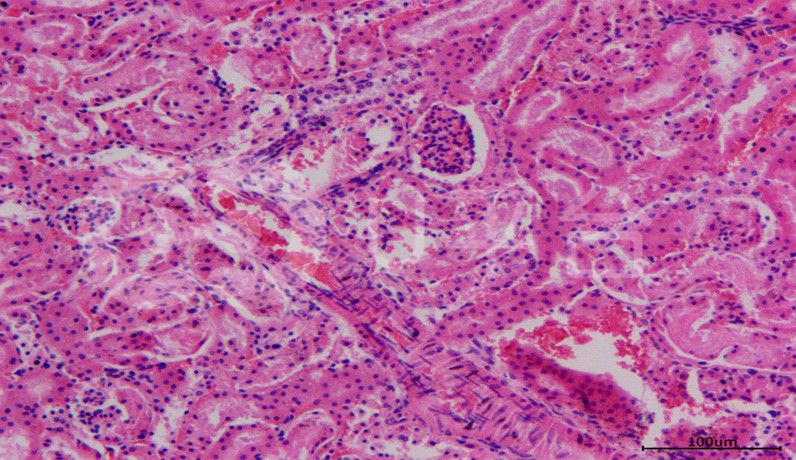

HE染色常見問題與處理方法由普拉特澤生物總結(jié)分享。一張優(yōu)質(zhì)的HE染色切片,應(yīng)該具備切片完整、無皺褶、細(xì)胞核著色清晰呈藍(lán)色、細(xì)胞質(zhì)呈鮮紅色、核仁核膜核內(nèi)染色質(zhì)顆粒清晰等特點,但多數(shù)切片染色新手即使是照書操作,仍然是破綻不斷,慘不忍睹。普拉特澤生物病理實驗平臺在承接大量的HE染色代做實驗后,積累豐富的操作經(jīng)驗,染過多種動植物、菌類組織樣本,總結(jié)了HE染色時常見的各種常見問題與解決方法。一起來看看吧!